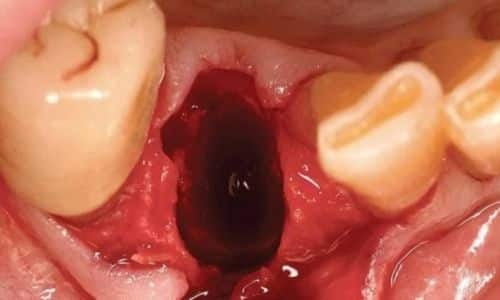

3.2. Phẫu Thuật Nha Khoa

Khi nhiễm trùng đã nghiêm trọng, phẫu thuật có thể cần thiết để làm sạch khu vực bị ảnh hưởng và giúp phục hồi hoàn toàn.

3.2.3. Phẫu Thuật Loại Bỏ Mô Viêm

Trong một số trường hợp, phẫu thuật để loại bỏ mô viêm xung quanh vùng xương hàm bị nhiễm trùng là không thể tránh khỏi.